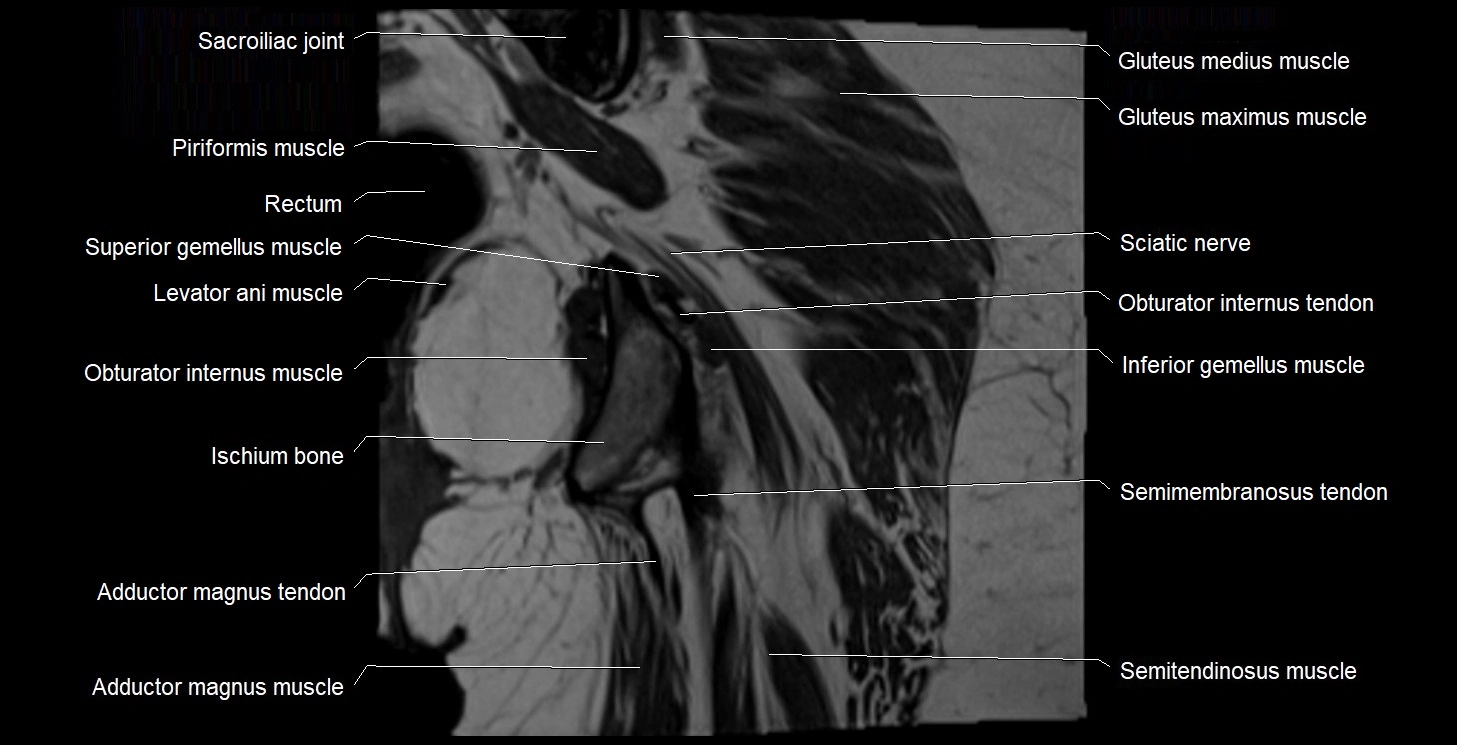

- Adductor magnus muscle

- Adductor minimus muscle

- Inferior gemellus muscle

- Ischium bone

- Levator ani muscle

- Obturator internus muscle

- Obturator internus tendon

- Rectum

- Semimembranosus tendon (proximal)

- Superior gemellus muscle